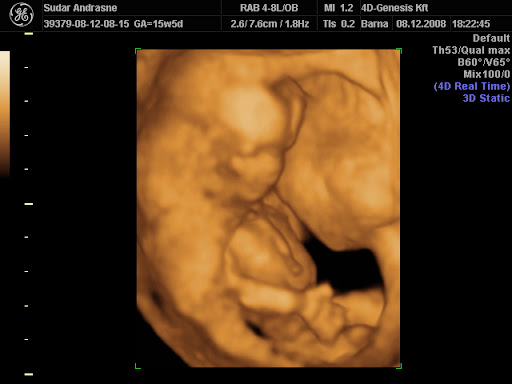

Mikor mentek legközelebb 4D-re? Remélem akkor már neked is látni fogják. Nekem azt mondta a nőci, hogy az egész egy türelemjáték...hál istennek a fél óránkba belefért!